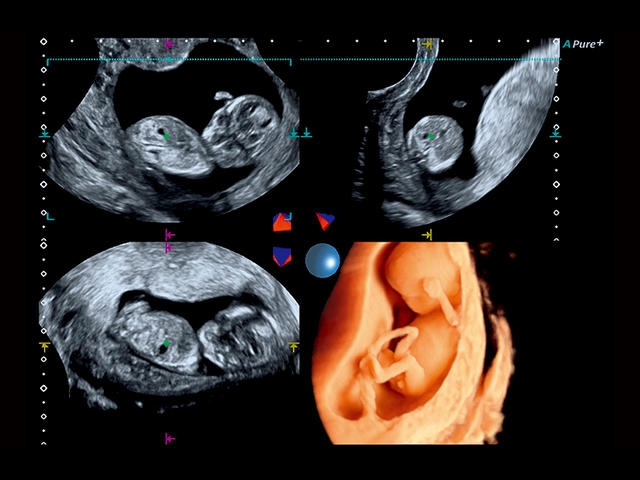

Aplio 500 – ультразвуковой сканер премиум класса, сочетающий в себе быстродействие диагностики и отличное качество визуализации. Более 30 датчиков на выбор, в т.ч. матричные, монокристаллические, 4D, эндоскопические для любых типов исследований. Ультразвуковой сканер позволяет изучать анатомические структуры в высоком разрешении.

Обновленная версия легендарного УЗ-сканера. Стационарный аппарат экспертного класса Aplio 500 Toshiba NEW, визуализирует анатомические структуры в высоком разрешении. Модель позволяет выявить микрокальцификаты, новообразования, нарушения в работе сердца, сосудов и мышц. Присутствует функция виртуальной эндоскопии, 4D-сканирования, эластометрии тканей, УЗИ с контрастированием. За повышение качества изображения отвечают технологии ApliPure и Superb Microvascular Imaging. Первая задействует возможности пространственного и частотного кодирования, формирует цельный визуальный ряд с сохранением клинических маркеров. Вторая улучшает отображение микрососудистого русла, используя доплеровский эффект. Модель оснащена 21-дюймовым монитором, имеет 4 активных порта. Возможно подключение педиатрических, интраоперационных, лапароскопических и чреспищеводных датчиков.

4D:

Да

STIC: